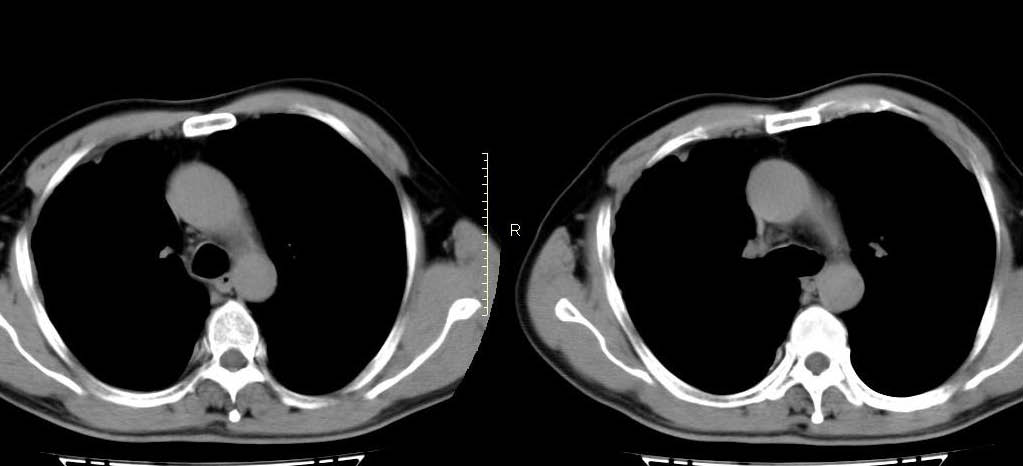

男,56岁,右侧腋窝下巨大软组织包块转移。欢迎讨论。

该病例为已经确诊的右侧恶性胸膜间皮瘤病例,有青石棉接触史,早期就是胸水,右侧胸壁“花边状改变”,心隔角区软组织阴影形成。近期右侧腋窝下巨大软组织包块,病检为转移瘤。图片没有完全考来,主要是给大家看一下胸膜间皮瘤的病例。,右侧

右侧腋窝下巨大软组织包块已经被切除后的ct片,该病例有多家医院较多的ct检查片。